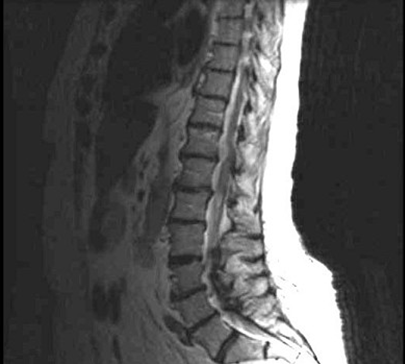

女,34岁,发热,腰部局限性疼痛、活动受限半月余,查体有压痛、叩痛,MRI检查如图,最可能的诊断为()

A.神经纤维瘤

B.脊髓内脓肿

C.神经鞘瘤

D.脊髓空洞

E.蛛网膜囊肿